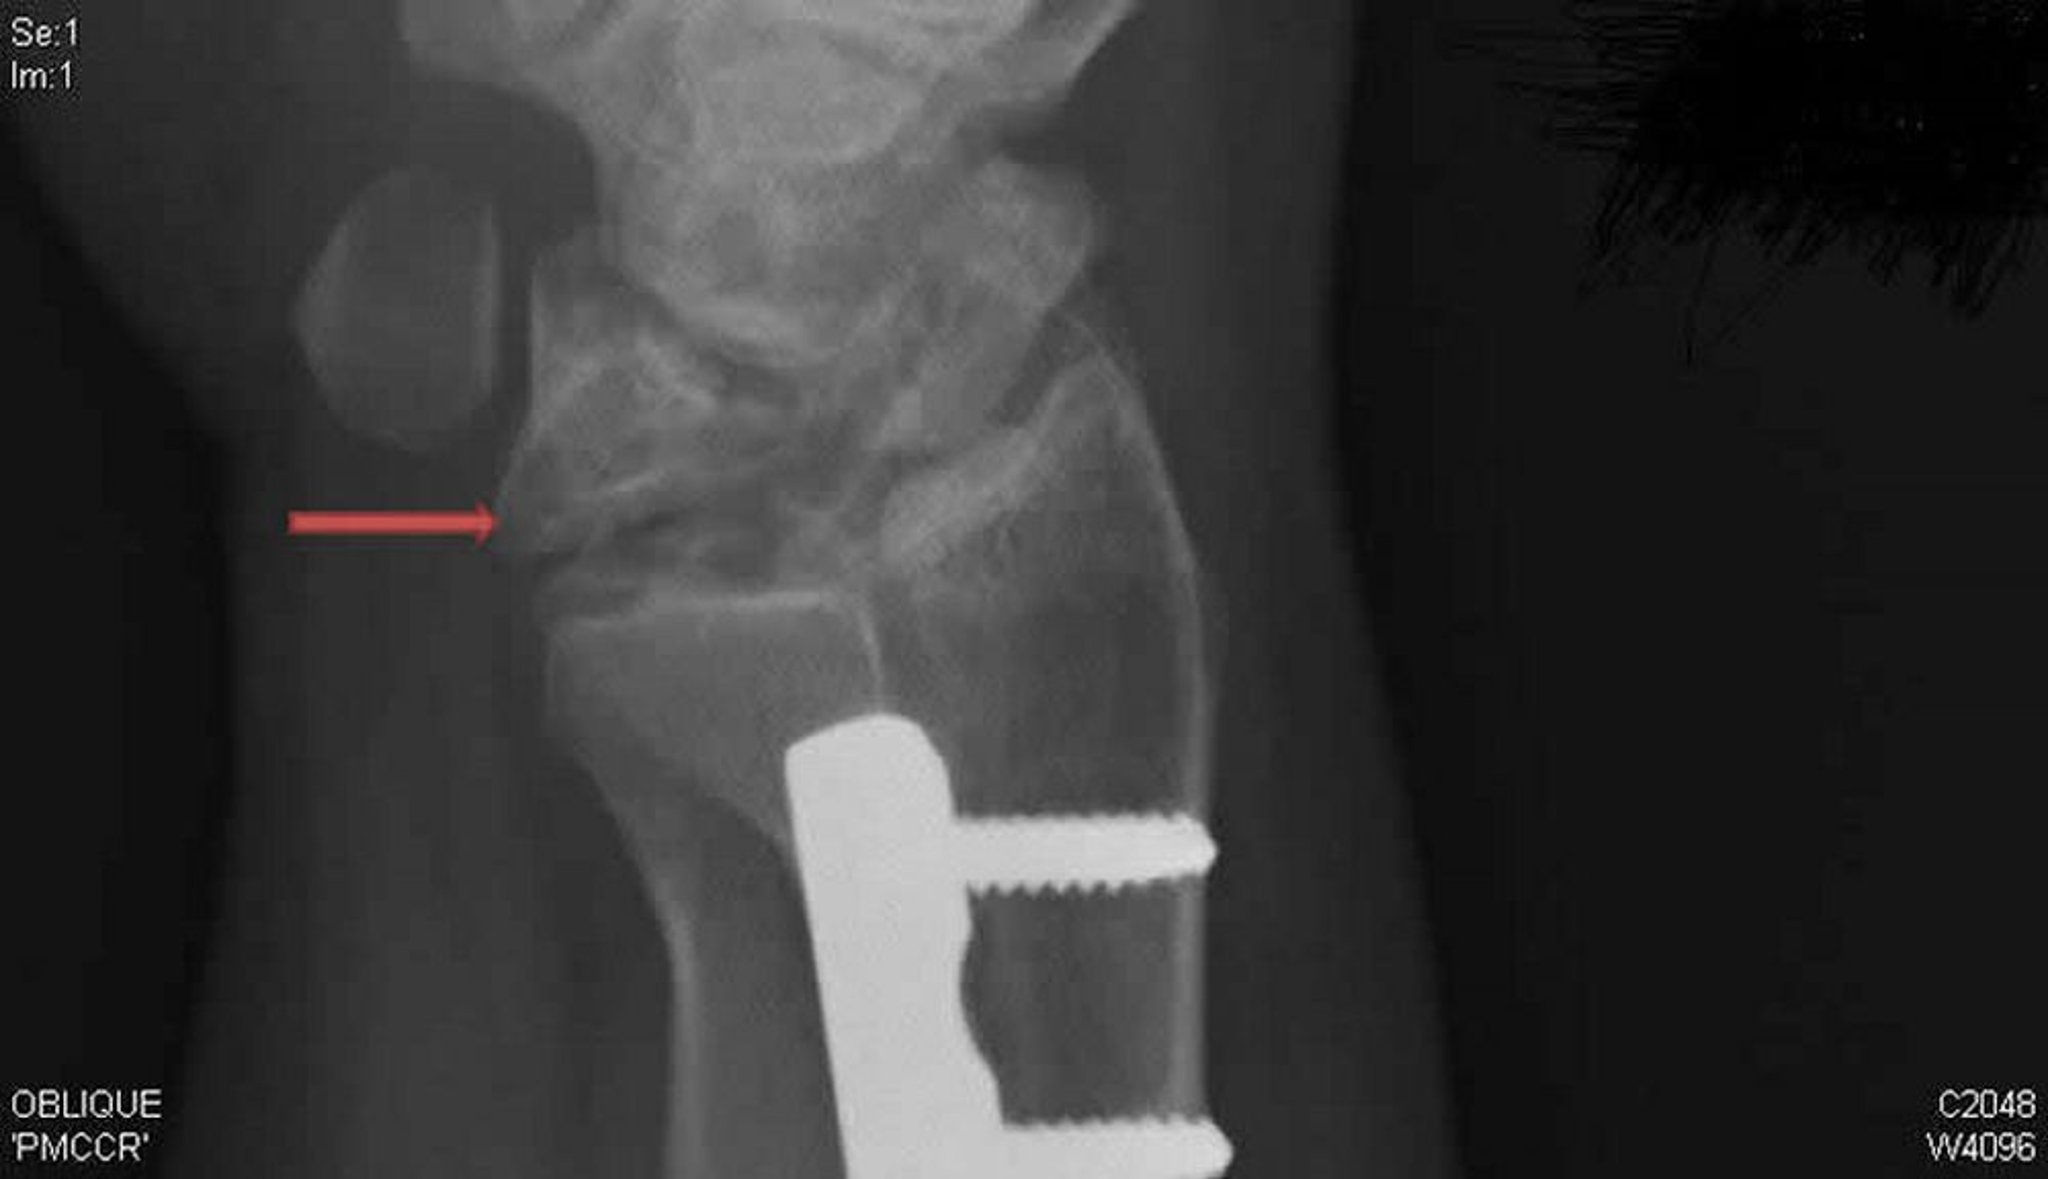

Morbo di Kienböck (RX in proiezione obliqua)

Questa RX obliqua del polso destro mostra il morbo di Kienböck. Si noti il crollo e la frammentazione dell'osso semilunare (freccia), che non era evidente in incidenza postero-anteriore.

RX cortesia di David R. Steinberg, MD.